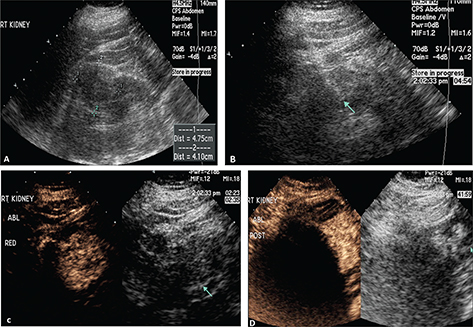

Occasionally a complete ablation cannot be obtained. This is often from significant blood flow to the mass or the mass adjacent to the collection system which acts as heat sinks and does not allow for adequate temperature to ablate the tumor. Figure 5 demonstrates a renal mass on the B-mode image (A) and the CEUS image (B). Immediately post-RFA, the B-mode (C) and CEUS (D) demonstrate minimal ablation of the tumor.

Figure 5. Failed ablation. Patient has history of prior left nephrectomy for RCC and presented with right renal mass. (A) Gray scale image of mass (arrow) pre-ablation. (B) CEUS demonstrating increased flow in tumor (arrow) at inferior pole of right kidney. (C) Gray scale image post-RFA of the mass (arrow). (D) CEUS post-RFA demonstrating flow throughout the tumor (arrow), indicating failed RFA.